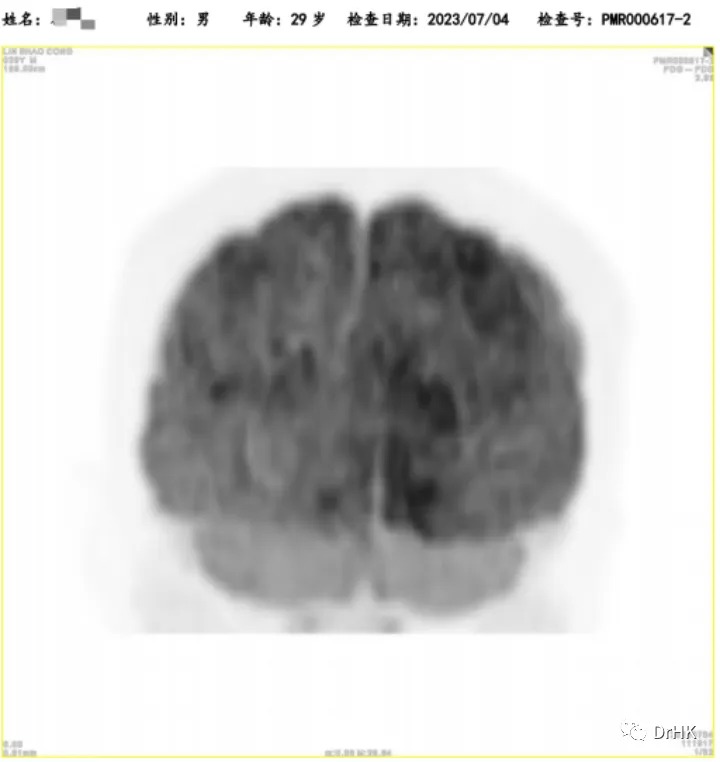

Starting from April 2, 2022, the patient was treated with the DA-TEDDi-R regimen combined with targeted therapy (ibrutinib + rituximab + dexamethasone + liposomal doxorubicin + etoposide + temozolomide + long-acting GCS + intrathecal Ara-C) for two cycles. After the treatment, the PET-CT assessment showed complete metabolic remission (the first complete remission since the onset of the disease), with a Deauville score of 2-3. Comparing this with the PET/CT imaging from our center on April 1, 2022, the liver lesion significantly decreased and the high metabolic activity disappeared; the left gluteus maximus lesion also disappeared. There were localized bone resorption and destructive changes in multiple bones (bilateral scapulae, clavicles, ribs, sternum, pelvic bones, and vertebrae), with some areas showing increased bone density, particularly in the left iliac bone. The bone marrow glucose metabolism was diffusely elevated, suggesting reactive changes post-treatment, and we recommended further evaluation with a bone marrow biopsy.

The patient was subsequently followed up regularly, with imaging evaluations completed six months and one year after the transplant. It is gratifying to report that the patient has maintained complete remission throughout this period. The PET images are shown below:

One-Year Post-Transplant Imaging Evaluation